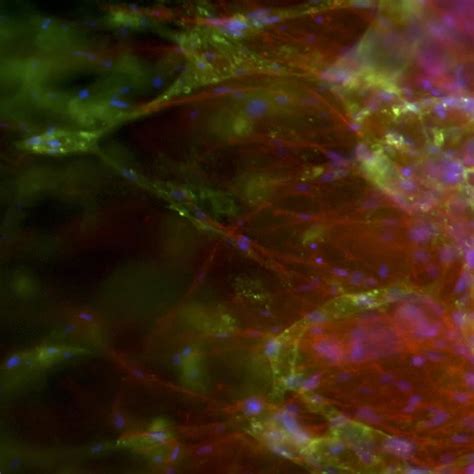

Capillaries In The Body

Source: humancirculatorysystemfall2014.weebly.com